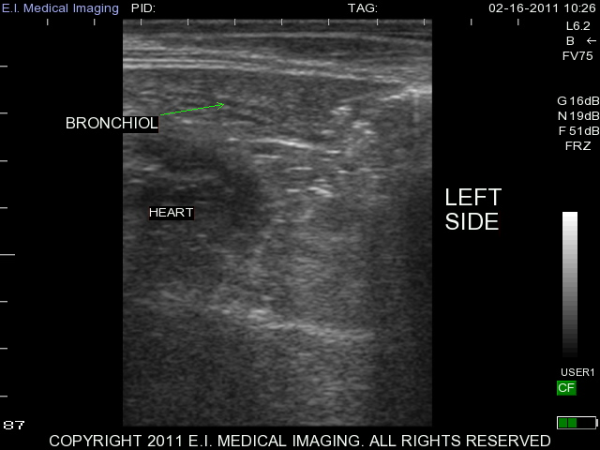

My name is Elizabeth Adams and I am a dairy practitioner in the central valley of California. Recently, I was able to use the IBEX PRO portable ultrasound to look at calf lungs for evidence of damage from calfhood pneumonia. In veterinary school, I scanned all of my patients with respiratory symptoms because it is a fast, non-invasive exam that provides a lot of information quickly. With ultrasound I can see healthy lungs, pleural effusion, atelectasis, consolidation and abscessation.

Ultrasound allows me to look at the surface of the lung; in a healthy lung, this is all we can see as the lung is full of air and doing its job. In a diseased lung, the surface of the lung is abnormal and allows penetration of the ultrasound waves deep into the lung parenchyma. Young calves require only the penetration of a 5-7.5MHz rectal ultrasound probe to see the evidence of damage from previous pneumonia.

Thanks to E.I. Medical Imaging's Research Loaner Program, I was able to scan lungs of calves at approximately three months of age. I am giving each calf a lung score based on the extent of lung damage seen on ultrasound. These heifers will then be followed out to their first freshening and I will see how well they perform in their first lactation. My hypothesis is that calves with extensive lung damage will not perform as well as their herdmates with healthy lungs. I plan to use ultrasound to help producers make more informed decisions when choosing calves to add to their herd.